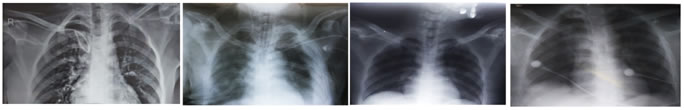

Image 1                                      Image 2                                                          Image 3                                        Image 4

Image 1: improper course of CVC – coiling; Image 2: malposition of CVC into Ipsilateral Internal jugular vein 1; Image 3: malposition of CVC into Ipsilateral Internal jugular vein 2; Image 4: More length of CVC into right atrium